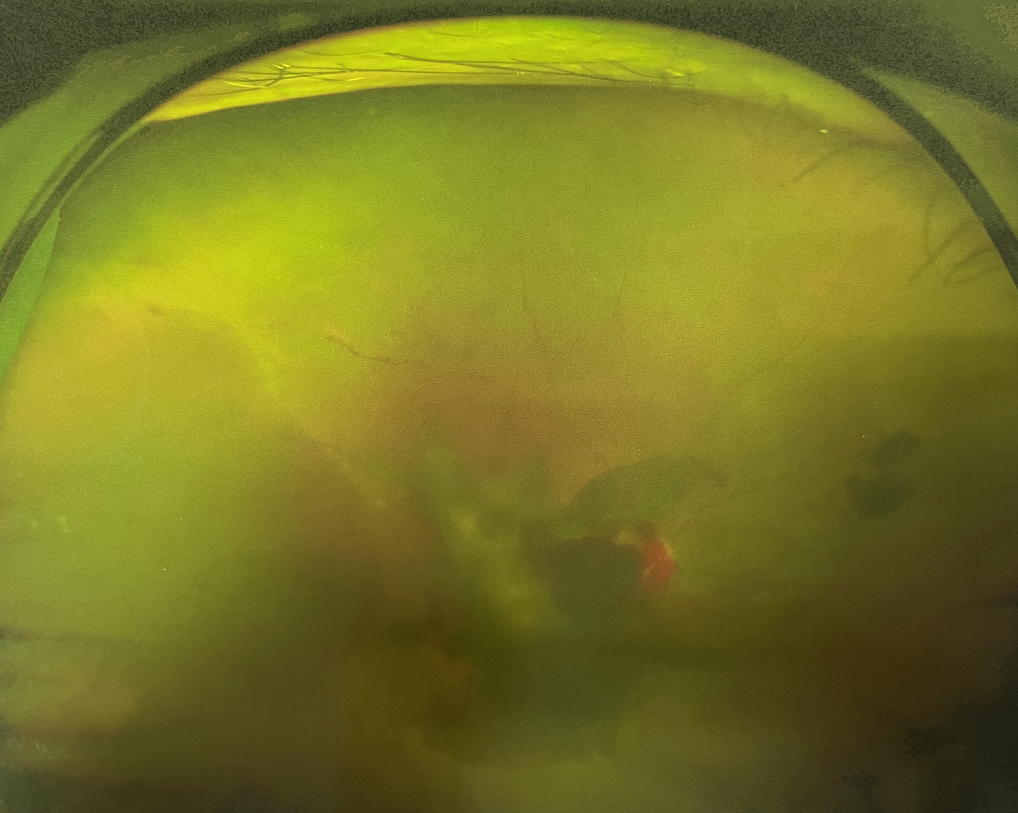

四十多歲的王女士,患高血壓病及Ⅱ型糖尿病多年,一直靠藥物控制血壓和血糖。去年,王女士右眼看手機(jī)時(shí)感覺視物不清,總感覺眼前有一層霧,視力也逐漸下降,于是來(lái)廈門大學(xué)附屬?gòu)B門眼科中心就診。

眼底病??茝埿』⑨t(yī)生檢查后,診斷王女士為“雙眼玻璃體積血、雙眼糖尿病視網(wǎng)膜病變V期”。(V期即5期,纖維增生期,出現(xiàn)纖維膜,可伴視網(wǎng)膜前出血或玻璃體出血。)

張小虎醫(yī)生為王女士進(jìn)行右眼玻璃體腔注藥術(shù),3天后進(jìn)行右眼23G玻璃體切割術(shù)后視力有所提升。

右眼術(shù)前